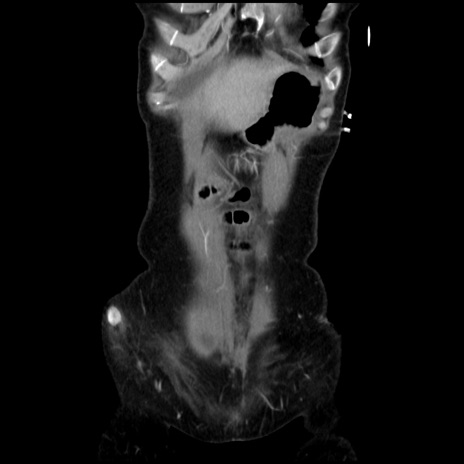

矢状断像